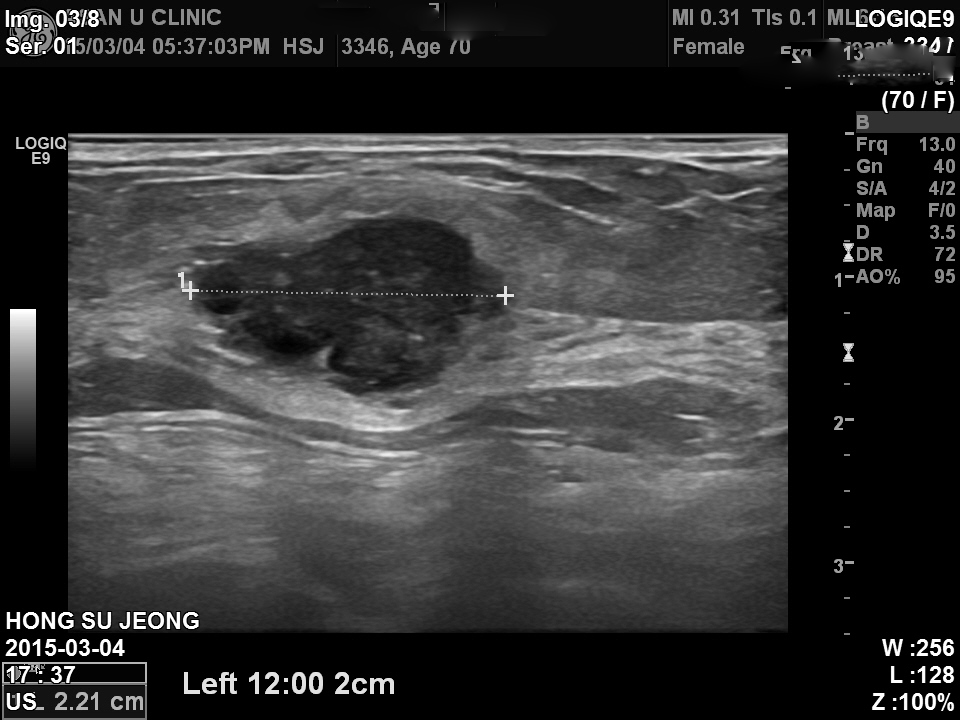

건강검진상 이상소견으로 내원하심.

촉진당시 만져지는 혹있음.

총조직검사상 좌측유방의 침윤성 유관암.